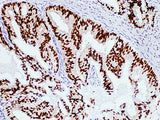

Applications IHC-P

Tissue Specificity Prostate cancer

Androgen receptor (AR) plays an important role in the development of prostate cancer. The positive expression of AR is related to the degree of prostate cancer tissue differentiation, and the patients with AR have significant effect on anti-hormone therapy. It is mainly used to detect prostate cancer and guide the treatment. At present, it can also be used in the research of breast cancer, esophageal cancer and other malignant tumors. Androgen receptor (AR) is highly expressed in well differentiated tumors, but low or no expression in poorly differentiated tumors.